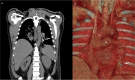

Accidental detachment of mechanical valve leaflet during implantation is a rare and potentially serious complication. When the lost leaflet cannot be found by direct visualisation, additional diagnostic procedures are necessary to detect it. Computer tomography is the best detection method, but the patient needs reoperation. We presented a patient in whom the detached leaflet migrated and became trapped into the left inferior pulmonary vein. The computed tomography (CT) scan was used to reveal leaflets, and successful extirpation was performed in the second operation.